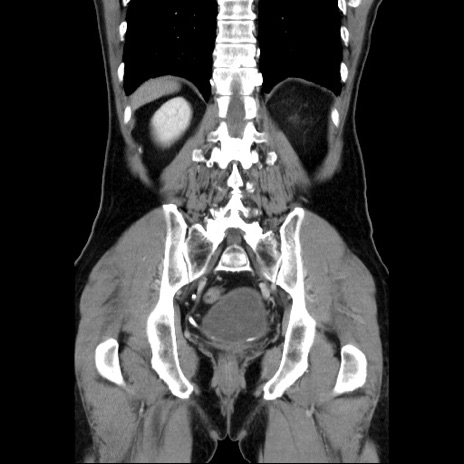

症例34(冠状断像)

【症例】60歳代 男性

【主訴】右鼠径部膨隆

【現病歴】1年程前より右鼠径部膨隆あり。自己にて還納可能だったため放置していた。3時間前より右鼠径部の脱出を認め、還納困難となり受診。

【既往歴】高血圧

【身体所見】右鼠径部に小児頭大の膨隆あり。弾性硬であり、用手還納は困難。左鼠径部にも膨隆を認める。脱出はなし。